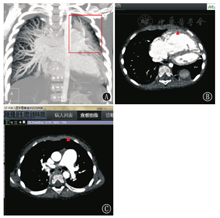

患儿,女,2岁,试管婴儿,第1胎,第2产,双胎之小,足月剖宫产分娩,同胞哥哥正常。患儿多发畸形(唇腭裂、脐疝、膈疝),面容可疑(眼距增宽、鼻梁低平),牙列不齐,生长发育明显落后。既往有反复"肺炎"病史。在8月龄时(2017年9月)因"房间隔缺损"来武汉亚洲心脏病医院就诊,入院后完善检查,心脏超声提示房间隔缺损(5 mm)、动脉导管未闭(2 mm)、PAH,第1次右心导管(表1)提示肺动脉压力处于临界状态、阻力明显升高,经过全面评估后认为患儿分流量不大,不是患者PAH的主要问题,暂无需手术治疗,需动态随访,可能是潜在PAH患者。随后,患儿分别于1岁、1岁10个月、1岁11个月时因"肺炎并心力衰竭"3次入院(表2),后3次入院时均有呼吸困难、端坐呼吸,心功能Ⅳ级,脑钠肽N末端前体(NT-proBNP)明显升高、脉搏血氧饱和度(SPO2)明显下降,经积极抗感染、维护心功能治疗后可下床活动。因患儿病情进展快、症状重,与先天性心脏缺损不相符,遂行心脏CT增强扫描进一步明确心脏畸形,心脏CT未发现新的心脏畸形,但提示左上肺发育不良(图1)、PAH征象明显(图2、图3),1岁11个月时复查右心导管(表1)提示PAH及阻力均明显升高。同时因患儿多发畸形、面容可疑、生长发育差、PAH病因不明,不排除遗传代谢性疾病可能,行全外显子(图4)和染色体畸变检查发现:FLNA突变(exon34:c.5417-1G>A),父母均未发生突变,为新发致病突变。该患儿于第4次住院期间,除常规抗感染及维护心功能治疗外,加用了小剂量肺血管扩张药物,强化了吸氧和患者家属教育工作,并告知最佳治疗方案为肺移植。患者末次出院时,NT-proBNP降至0.900 pg/L左右,SPO2上升至93%左右。出院后间断吸氧、继续服药,但因经济原因未考虑肺移植,于2.5岁时死亡。